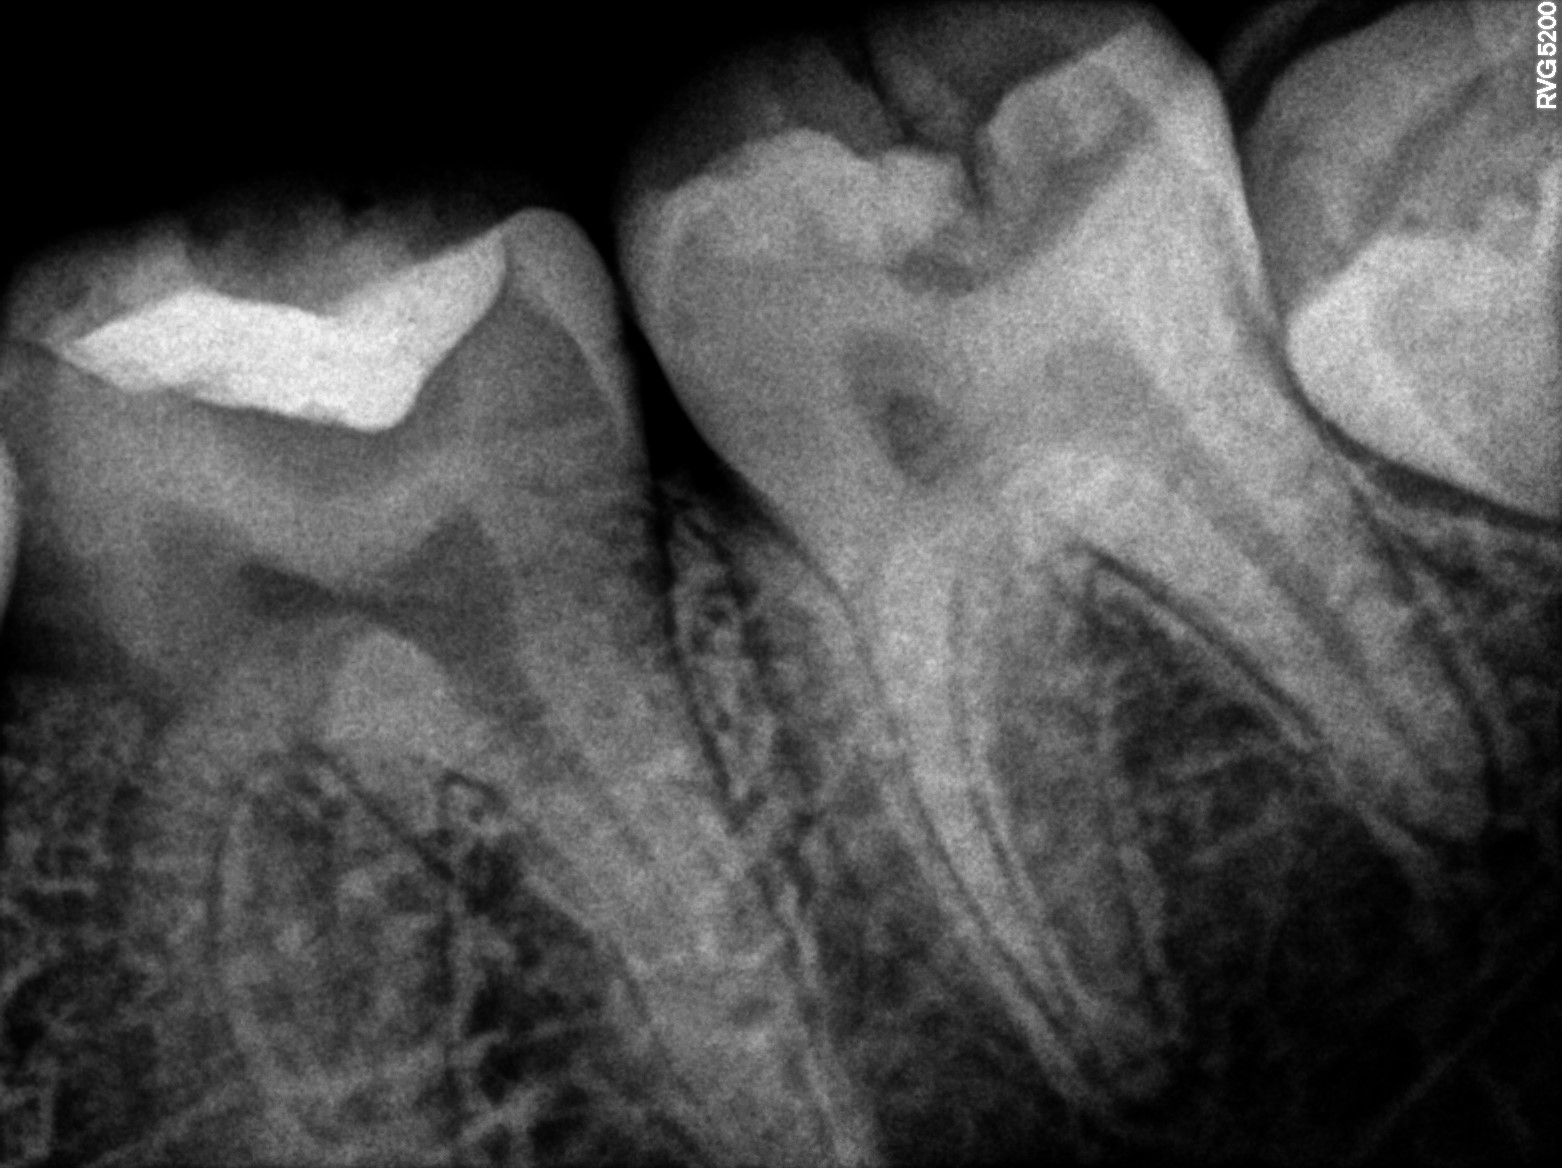

Dental Radiographs FHIR: DocumentReference · LOINC 24641-7

R54.jpg

24641-7